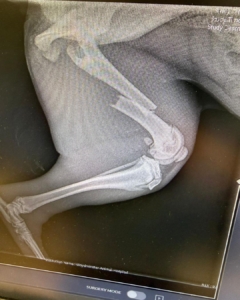

We’re happy to share that Dixie, our 5-month-old pup, is currently healing in her foster home after undergoing surgery to repair her broken leg. Despite the tough circumstances of being accidentally kicked by a horse, she’s showing incredible strength!

Meet Dixie, a sweet 5-month-old puppy who needs our help! Unfortunately, Dixie had an unfortunate encounter with a horse and injured her leg, resulting in a fracture. To give her the chance at a happy, healthy life, she requires surgery to repair her leg, which will cost approximately $2,000.